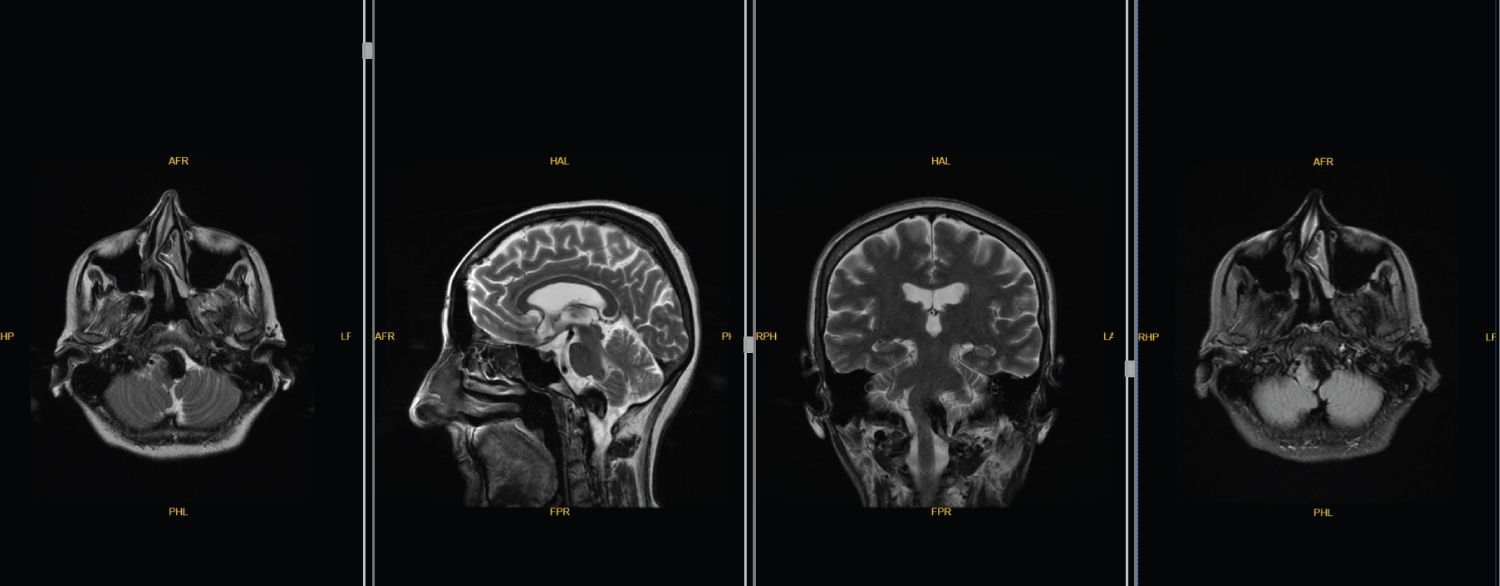

After 2 months of the operation, the patient had increased white phlegm and her choking cough was continuing. Furthermore, the patient's right limb muscle strength was improved compared with that pre embolization and the patient has Medical Research Council grade 5 muscle strength in the right limb. Three months after embolization, re examination of the head MRI and MRA revealed that the aneurysm was completely occluded [Raymond Roy classification, Class I [7]]; although, the brainstem was still compressed when comparing with the pre-embolization Mri (Figure 3). At 12 months after surgery, her phlegm was markedly improved and discontinued with the medical drugs. Cough and hoarseness disappeared. Re examination of DSA revealed no aneurysm recurrence [Raymond Roy classification, Class I [7]] and no stenosis in the parent artery on MRI (Figure 4) and computer tomography angiography (Figure 5). The modified Rankin scale score [8] of the patient is 1 point.

Figure 3: At 12 months after surgery, her phlegm was markedly improved and discontinued with the medical drugs. View Figure 3

Figure 4: No stenosis in the parent artery on MRI. View Figure 4